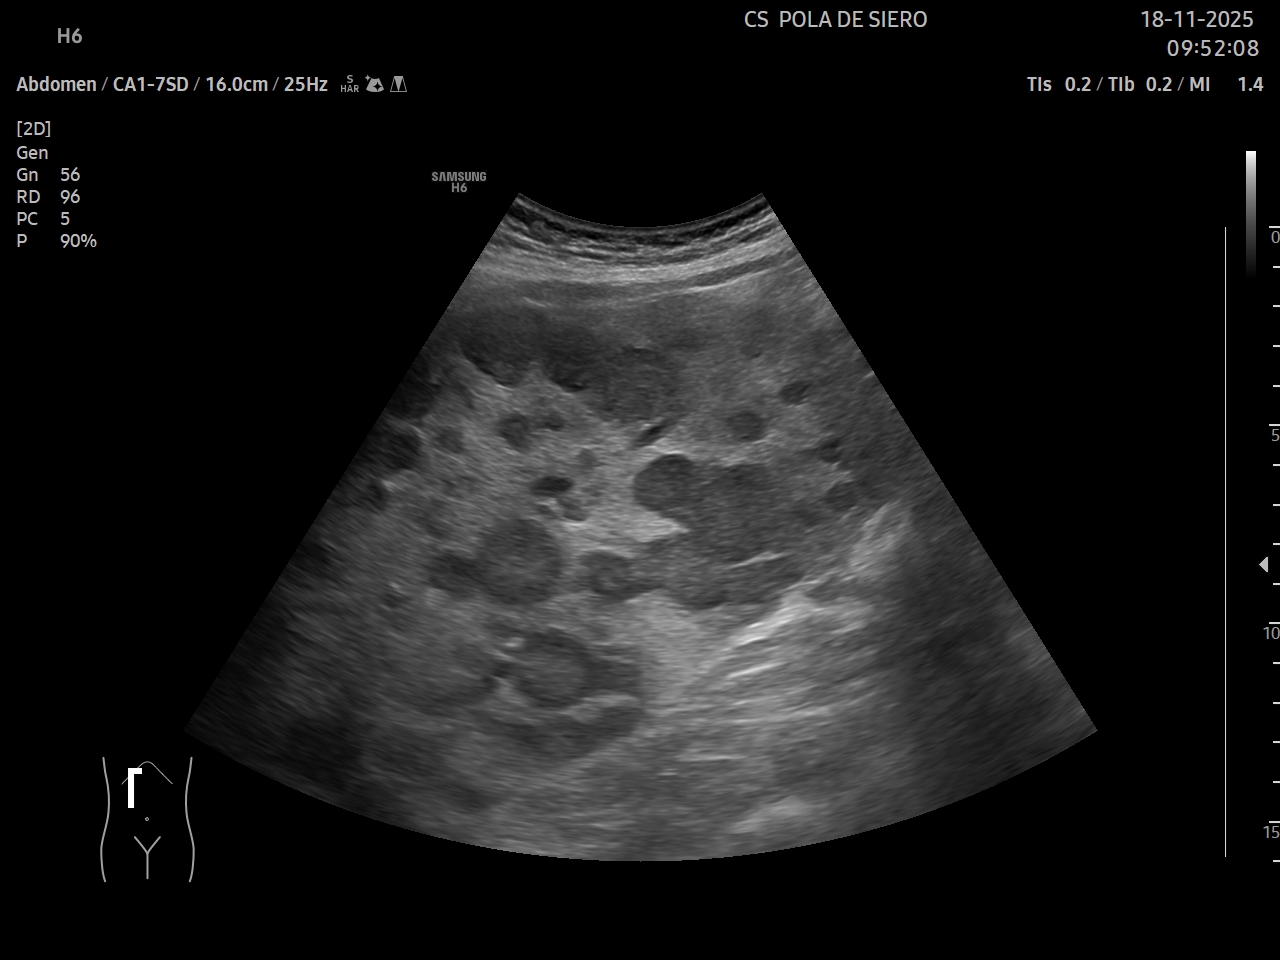

Ecografía clínica: múltiples imágenes hipoecoicas que afectan todo el parénquima hepático, vesícula alitiásica. Porta desplazada, permeable. Flujo hepatópeto y riñones normales. Bazo de tamaño normal. Vejiga no replecionada. No líquido libre.

Juicio clínico: metástasis hepáticas múltiples.

Diagnóstico diferencial: adenomas hepáticos múltiples; hepatocarcinoma multifocal.